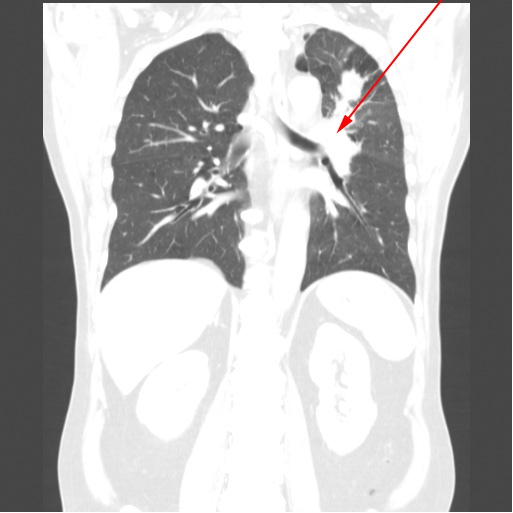

Røntgen (oven for) og CT-optagelse (neden for) af den samme patients lunger med få dages mellemrum. Begge billeder viser stor lungetumor i venstre overlap (røde pile).